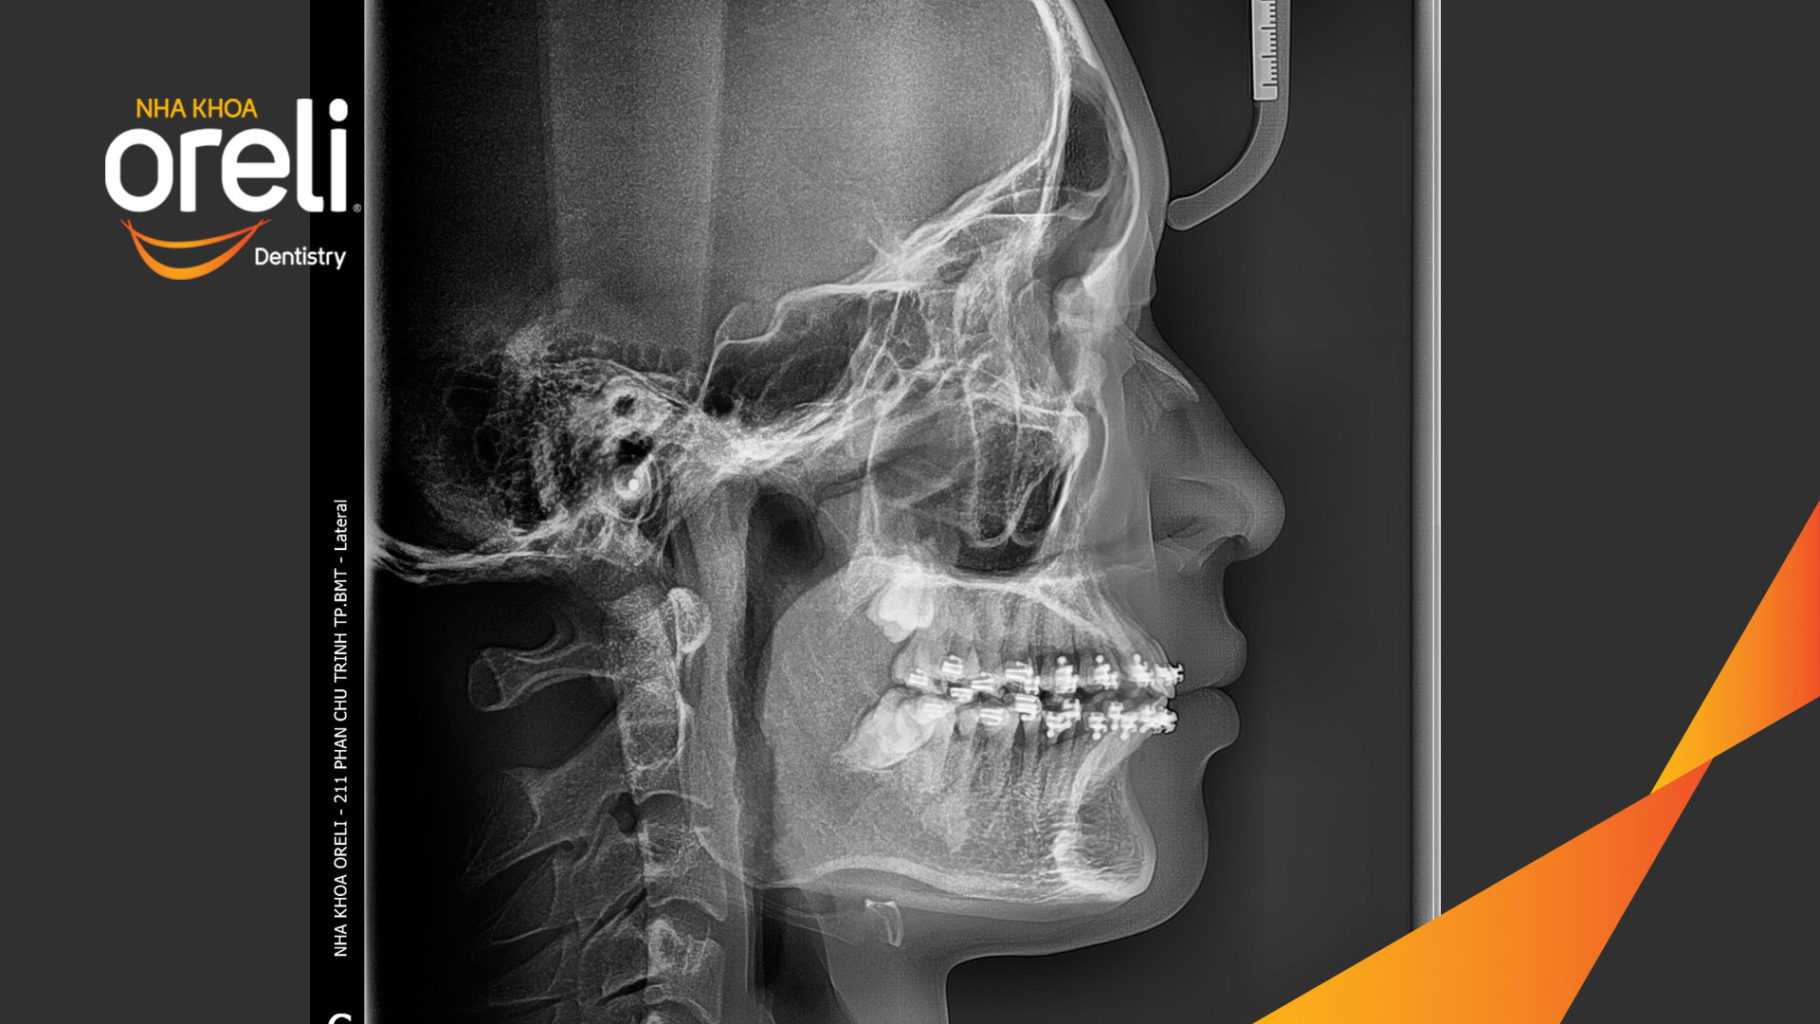

Ca niềng chỉnh cắn sâu hô lùi cằm cho kết quả nụ cười và góc nghiêng đẹp ở Oreli

Ca niềng răng cắn sâu phục hồi ăn nhai và thẩm mỹ nụ cười. Kết quả thực tế trước và sau điều trị tại Nha khoa Oreli.

Giải pháp: làm đều chỉnh khớp cắn sâu không nhổ răng

Thời gian: 36 tháng

Kết quả: khớp cắn đúng, cằm tiến ra trước với mặt nghiêng đẹp